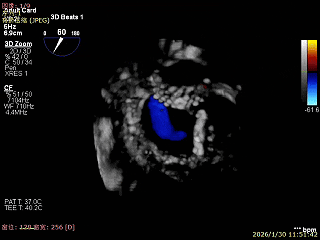

3D Enface下组织桥稳定残余外侧前叶脱垂

3D Enface上彩可见夹子内侧无反流,残余外侧反流

3D Enface下组织桥稳定无反流

夹子释放后,反流基本消失